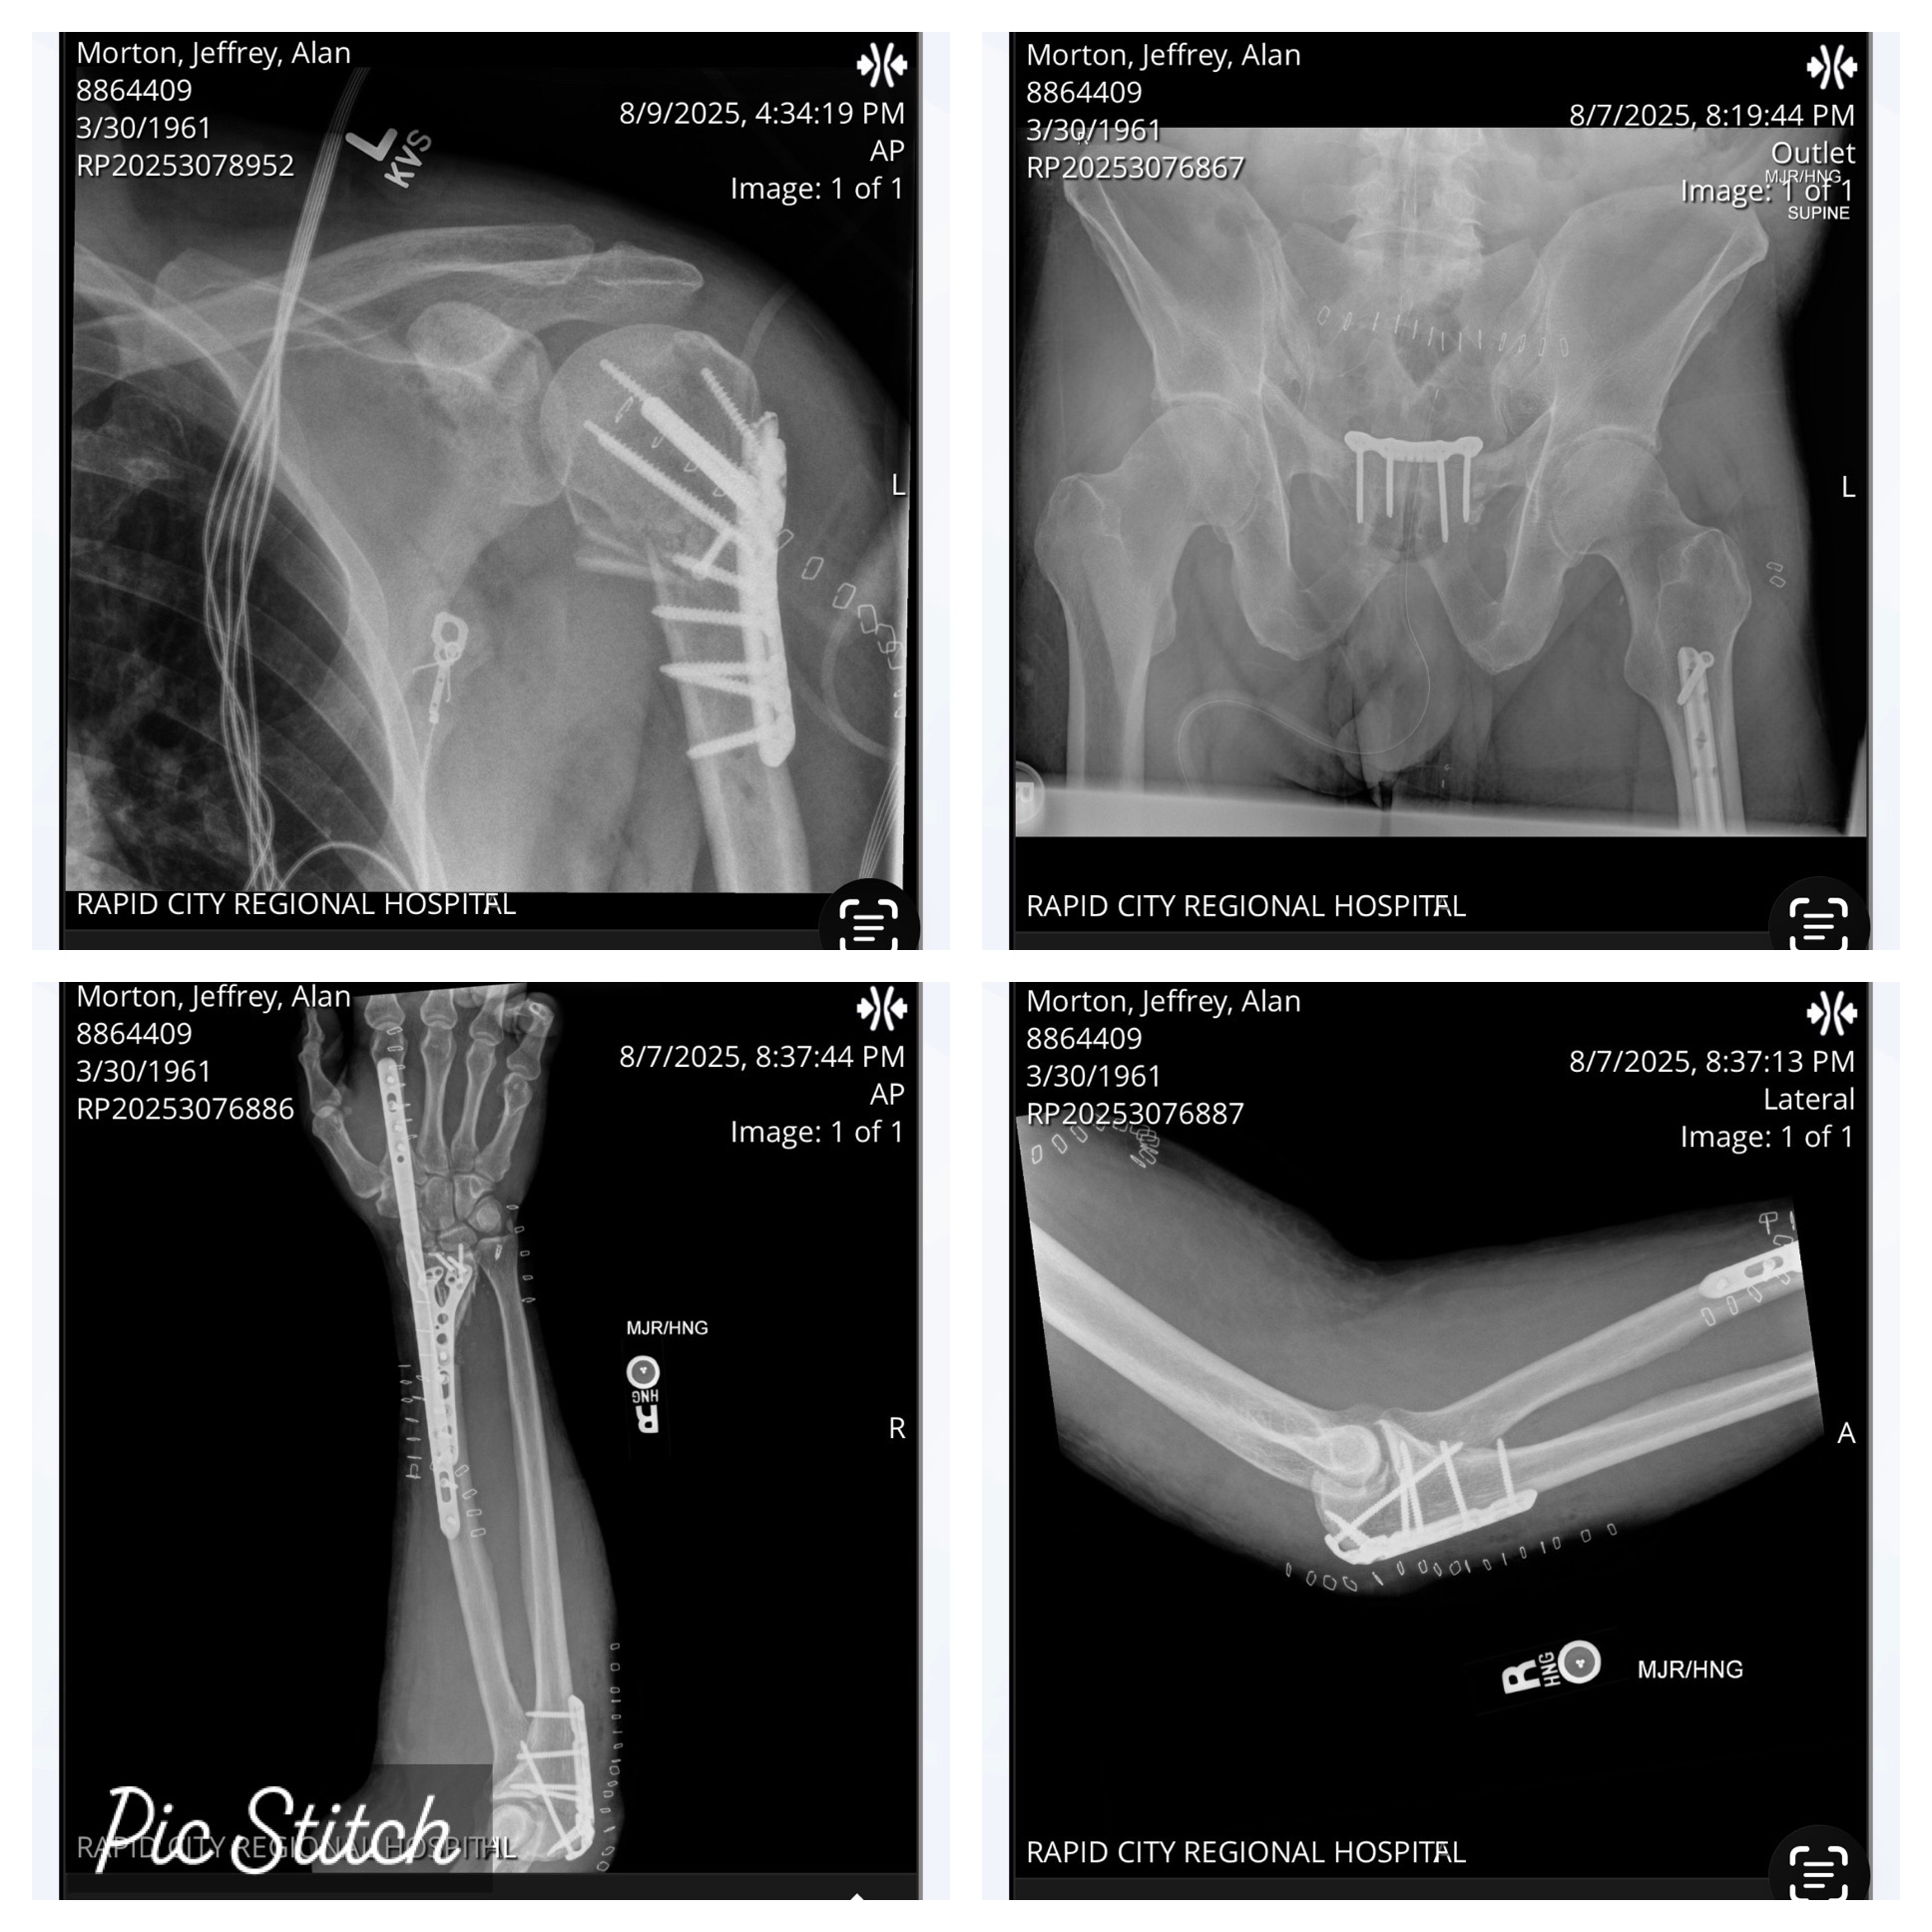

• Compound fractures of radius and ulna on right wrist requiring 13 cadaver bones, a plate, and screws in right arm. Three surgeries on wrist. The intensity blew apart his elbow which now has a plate and six screws.

• Fractured right scapula, torn rotator cuff, and supraspinatus in the right shoulder leaving right arm numb.

• Pelvis fractured requiring a plate.

• Ball of humerus bone completely broke in half requiring a plate, 12 screws, four of which came loose and needed to be removed.